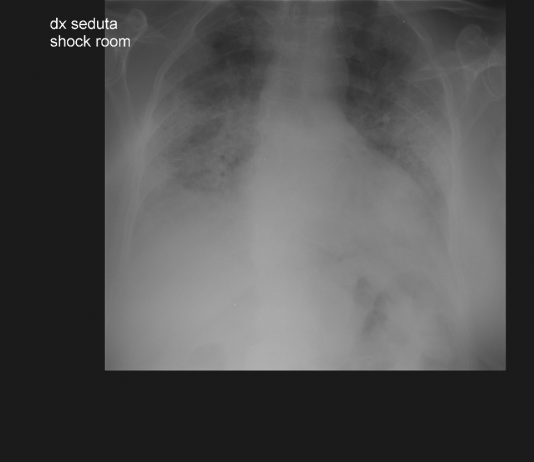

73-year-old female

patient with fever and respiratory distress.

The patient was intubated in the...